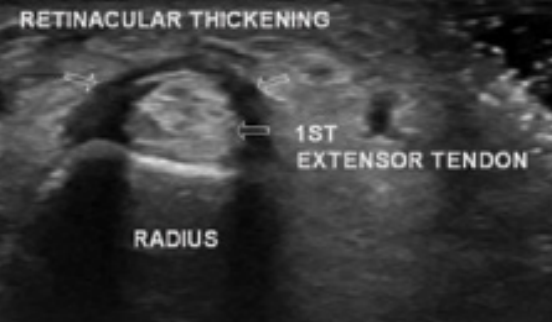

De Quervain’s Tenosynovitis or Syndrome refers to the painful wrist and thumb symptoms that occur on the thumb side of the wrist. De Quervain’s Tenosynovitis pain is normally due to thickening of the tendons of the Abductor Pollicis Longus (APL) and Extensor Pollicis Brevis (EPB) muscles through the forearm. As the thickened tendons pass through a tunnel (the first dorsal compartment), the constant friction causes thickening and degeneration or scar tissue (as well as inflammation) to occur to the tendon sheath itself – which in turn compresses the nerve and can cause a strong, shooting type wrist pain.